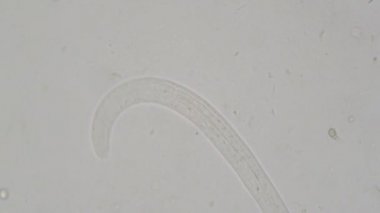

Eser Sahibi: Ivan Baranov